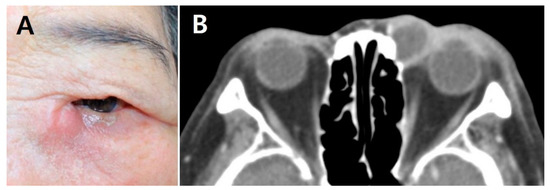

A retrospective review of medical records was performed on consecutive patients who underwent EnDCR for AD with cellulitis between May 2010 and June 2020 at Chungnam National University Hospital. The diagnosis of AD was based on the clinical presentations with radiologic findings. Patients with painful swelling of the lacrimal sac area with marked medial canthal inflammation were identified. Facial computed tomography was performed in all patients with clinical evidence of AD. Figure 1 shows the representative facial photograph and the computed tomography imaging of an 80-year-old woman with AD. Patients who underwent early EnDCR within 1 week after diagnosis were included. The minimum required follow-up period after surgery was 6 months. Patients who could not be hospitalized on the day of diagnosis were excluded. Patients with a history of lacrimal, maxillofacial, or sinus surgery; facial trauma; or a neoplasm involving the lacrimal drainage system were excluded.

Figure 1. Representative facial photograph and computed tomography (CT) imaging of an AD patient. (A) External photograph of an 80-year-old woman who presented with pain, redness, and swelling around left the lacrimal sac area. (B) CT scan showing peripheral enhancing cystic lesion in the left medial canthal area with enhancing soft tissue swelling in the adjacent periorbital area.